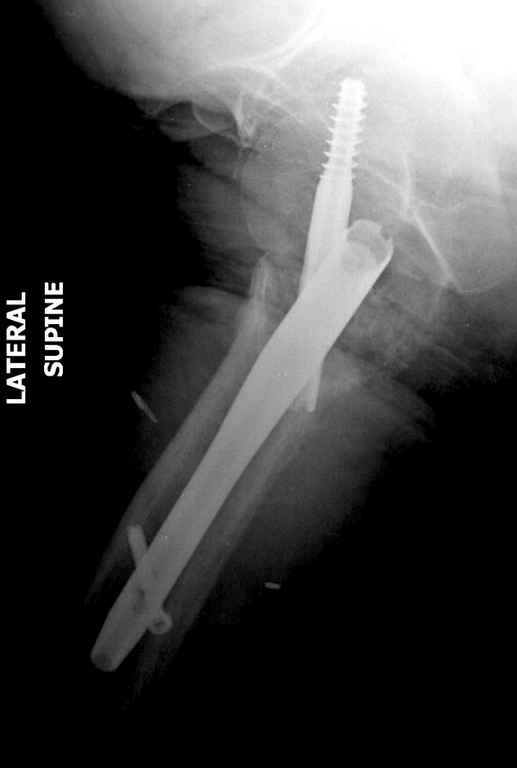

Перелом тут больше подвертельный. Нагрузка без торцевого упора на уровне перелома привела к телескопированию отломков на стержне. Ну и варус небольшой тоже свою лепту внес - если бы его не было, контактирующие латеральные стенки обоих отломков предотвратили бы укорочение, да и срослось бы за пару месяцев. А раз не срослось, упора отломков нет, более слабым местом оказались не нижние винты, а кость в головке и шейке. Так что надо было хотя бы удалить нижние винты до начала полной нагрузки.

На мой взгляд, причиной телескопирования явилось несоответствие диаметра гамма нэйл с диаметром канала подвертельного отдела бедра: обратите внимание на величину протрузии шеечного винта и величину медиализации дистального фрагмента - они одинаковы, смещение или телескопирование фрагментов происходило до того момента, пока гамма нэйл не упёрся в медиальный кортекс и образовалось пространство между латеральным

кортексом и латеральной поверхностью гвоздя.

Диаметр гаммы в диафизарной части ~11 мм. А диаметр канала, тем более у пожилых с остеопорозом, может быть мм 15. Даже рассверливать обычно не приходится, после формирования широкого канала в вертельной области можно сразу толкать гвоздь, он влетает, как карандаш в стакан. Так что соответствия диаметров не бывает никогда. Однако представленная ситуация случается далеко не каждый раз. Если гвоздь в центральном отломке входит чуть медиальнее верхушки вертела, и идет вдоль передне-латеральной стенки центрального отломка, то все будет хорошо.

Здраствуйте. По данному снимку видно 2-а основных момента которые привели к протрузии винта в вертлужную впадину: 1) шеечный винт дистальной поверхностью наружнего края "зацепился" за латеральный кортикал бедра, это не дало сработать динамической системе гвоздь-винт. 2) лучьше шеечный винт проводить ближе к дуге Адамса, там болееплотная костная ткань. Решенее: как подготовка к эндопротезированию, реостеосинтез, можно такой же системой, но с учетом упомянутых моментов, максимальное безнагрузочное ЛФК (без боли).